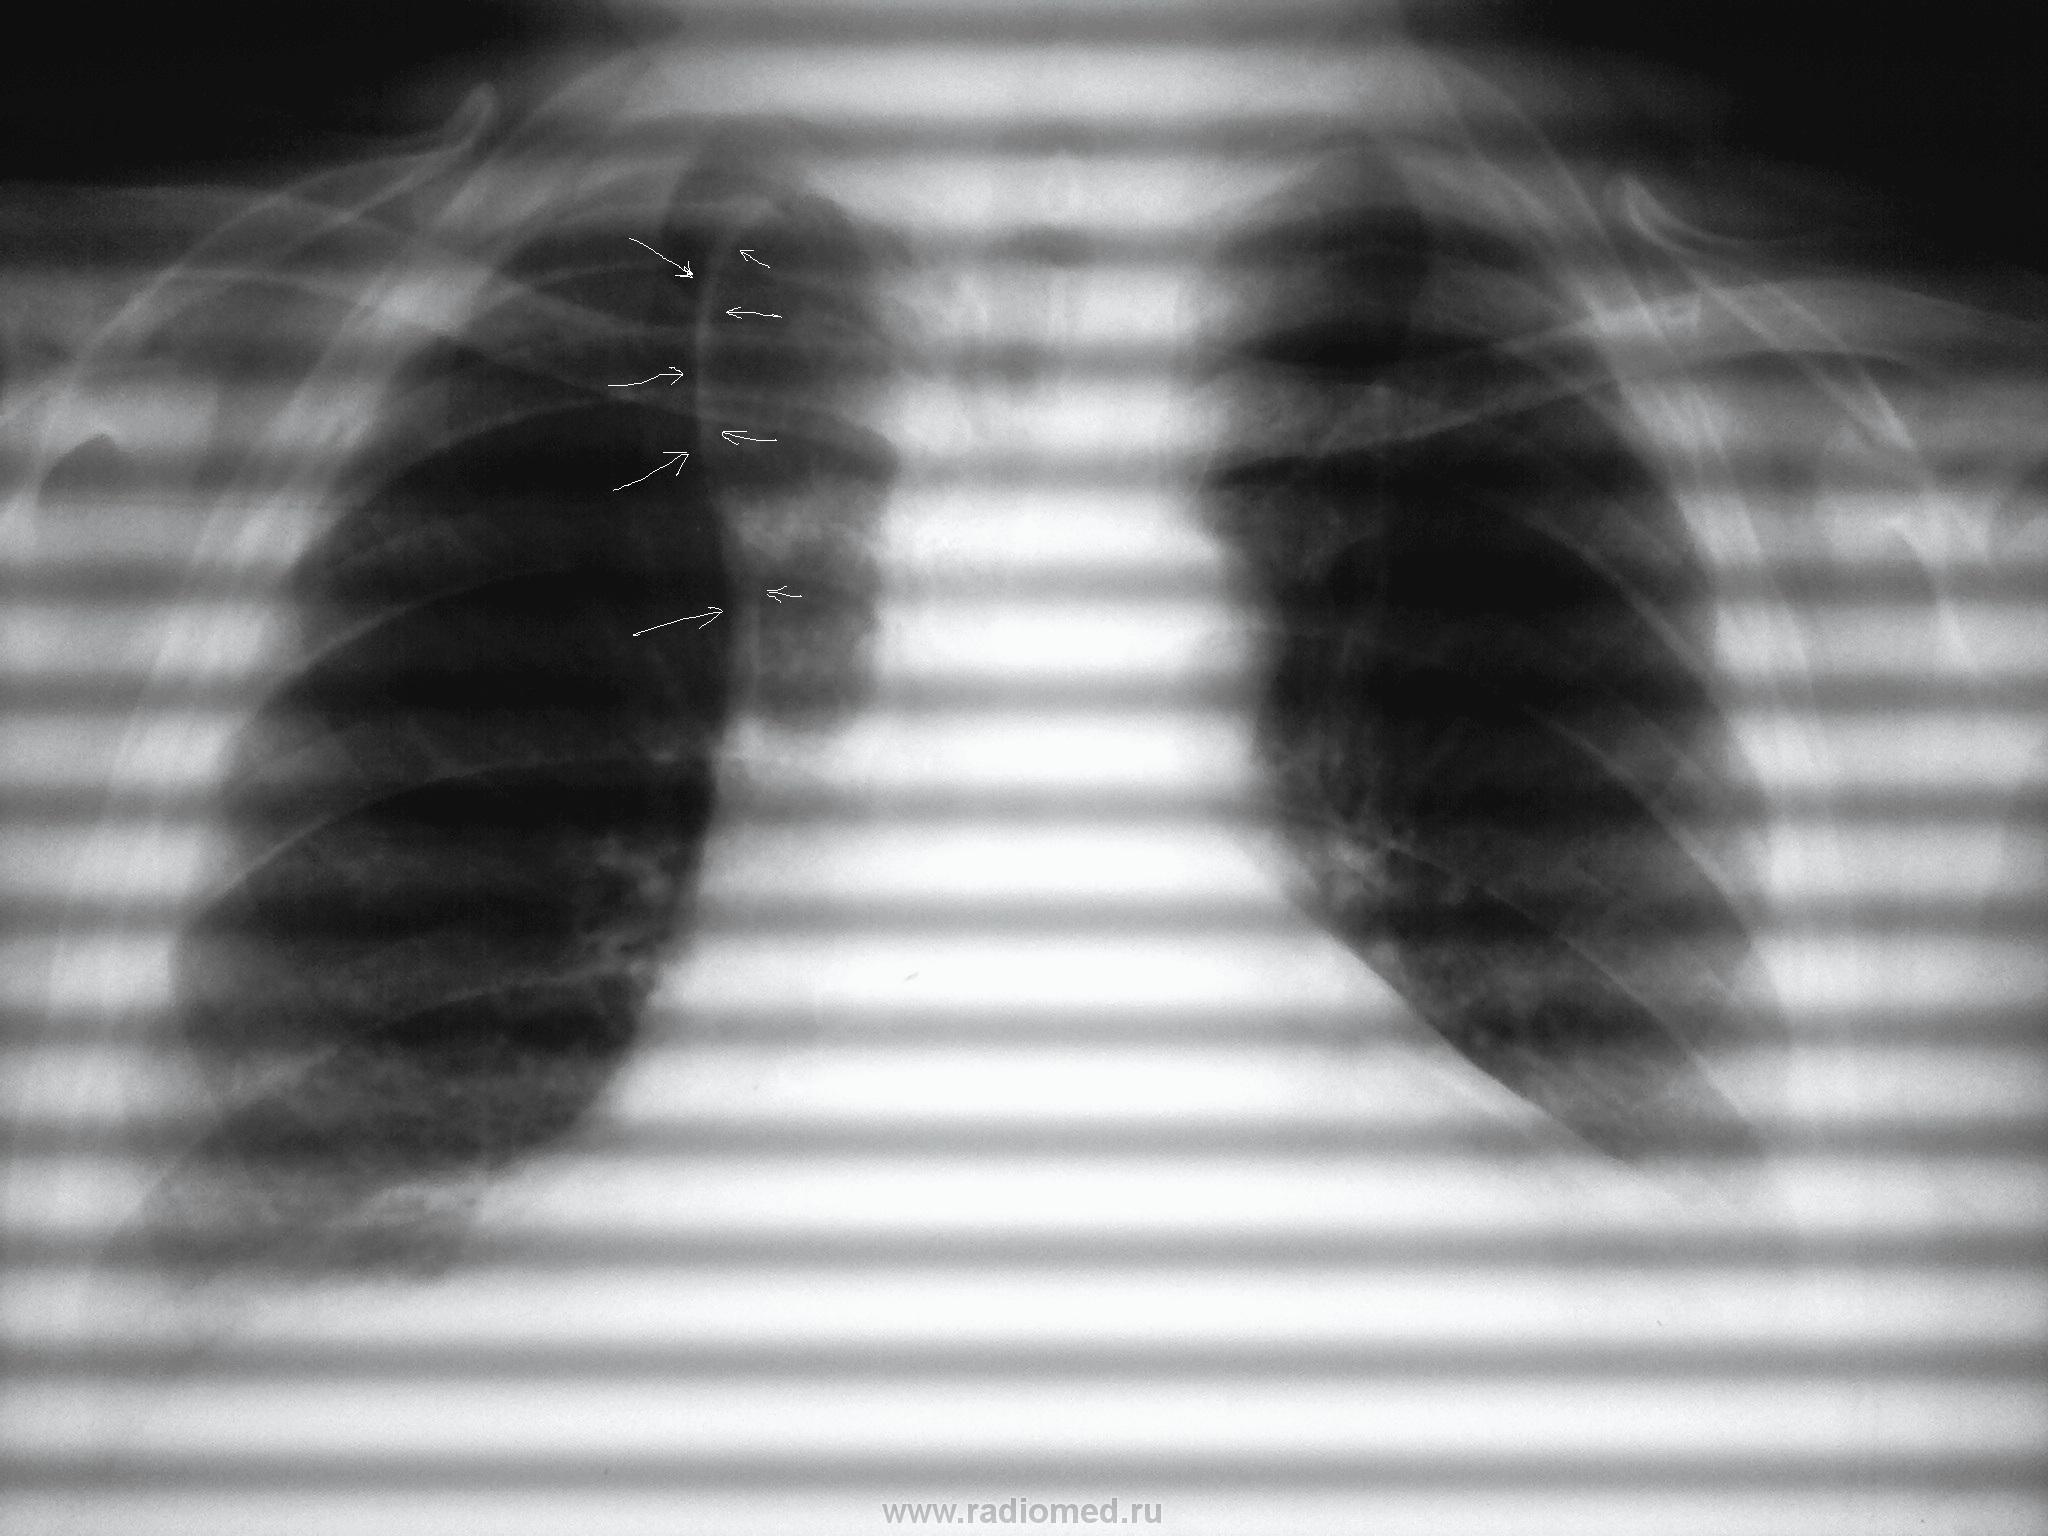

Уважаемые коллеги . помогите разобратся . Пациентка 1951 года , у нее сердечная недостаточность. в течение последних недель больная жалуется на одышку и кашель.

Пристеночные плевральные наложения с 2-х сторон, более выраженные справа ( отложения жира паракостально ?). Выраженная дилятация сердца.Доля непарной вены справа ?, но очень уж утолщена плевра (...?).

Cor расширено влева за счет дилятации ЛЖ-верхушка опущена вниз,талия corсглажена-Rg-признаки паталогии аортального клапана (вероятнее,недостаточность),2 дуга слева несколько удлинена (будем считать.что установка практически ровная)-венозный застой.Аорта в форме "клюва".Увеличение cor вправо в данном случае вероятнее счет ПЖ -нужна боковая.Частично определяется v.cava sup.- застой в большом круге кровообращения.Изменения сосудистого рисунка в легких может протекать по 5 вариантам.В даном случае,т.к. снимок не кач.,но можно предполагать начинающийся венозный застой-перераспределение кровотока в верхние отделы-сосуды расширены,корни несколько тяжисты-отсюда и отдышка,кашель-жидкой части крови нужно же куда-то деваться-пропотевает в бронхи.деформация легочного рисунка преимущественно в н.отделах за счет перибронх. и периваск уплотнений.З-ие: Rg-пр недостаточности аортального клапана с явлением венозного застоя в легких. P.S.думаю,что нужно исключать и патологию трикуспидального клапана.P.S.S. Доб. доля v.az.,плевральные наслоения в перед. реберно-диафр. синусах.

А я не согласна с недостаточностью аортального клапана. Если и есть, то только в комбинации с пороком митрального клапана. Форма сердца больше склоняется к митральной, справа вторая дуга тоже удлиненна, что может говорить об увеличении левого предсердия или правого желудочка (к сожалению, не хватает снимков, сюда бы правый и левый косые и было бы видно замечательно) Слева первая дуга несколько более выдается, но настолько сильной деформации, какая характерна для аортальной недостаточности, я здесь не вижу.

Попробуйте изменить настройки телефона при съемке, чтоб полос не было. А стрелки - похоже на v.azygos в дупликатуре плевры.

Стрелки указывают на добавочную долю v.axygos.

Чтобы за долю непарной вены не принять стенку расширенного пищевода - там ведь похоже на уровень...